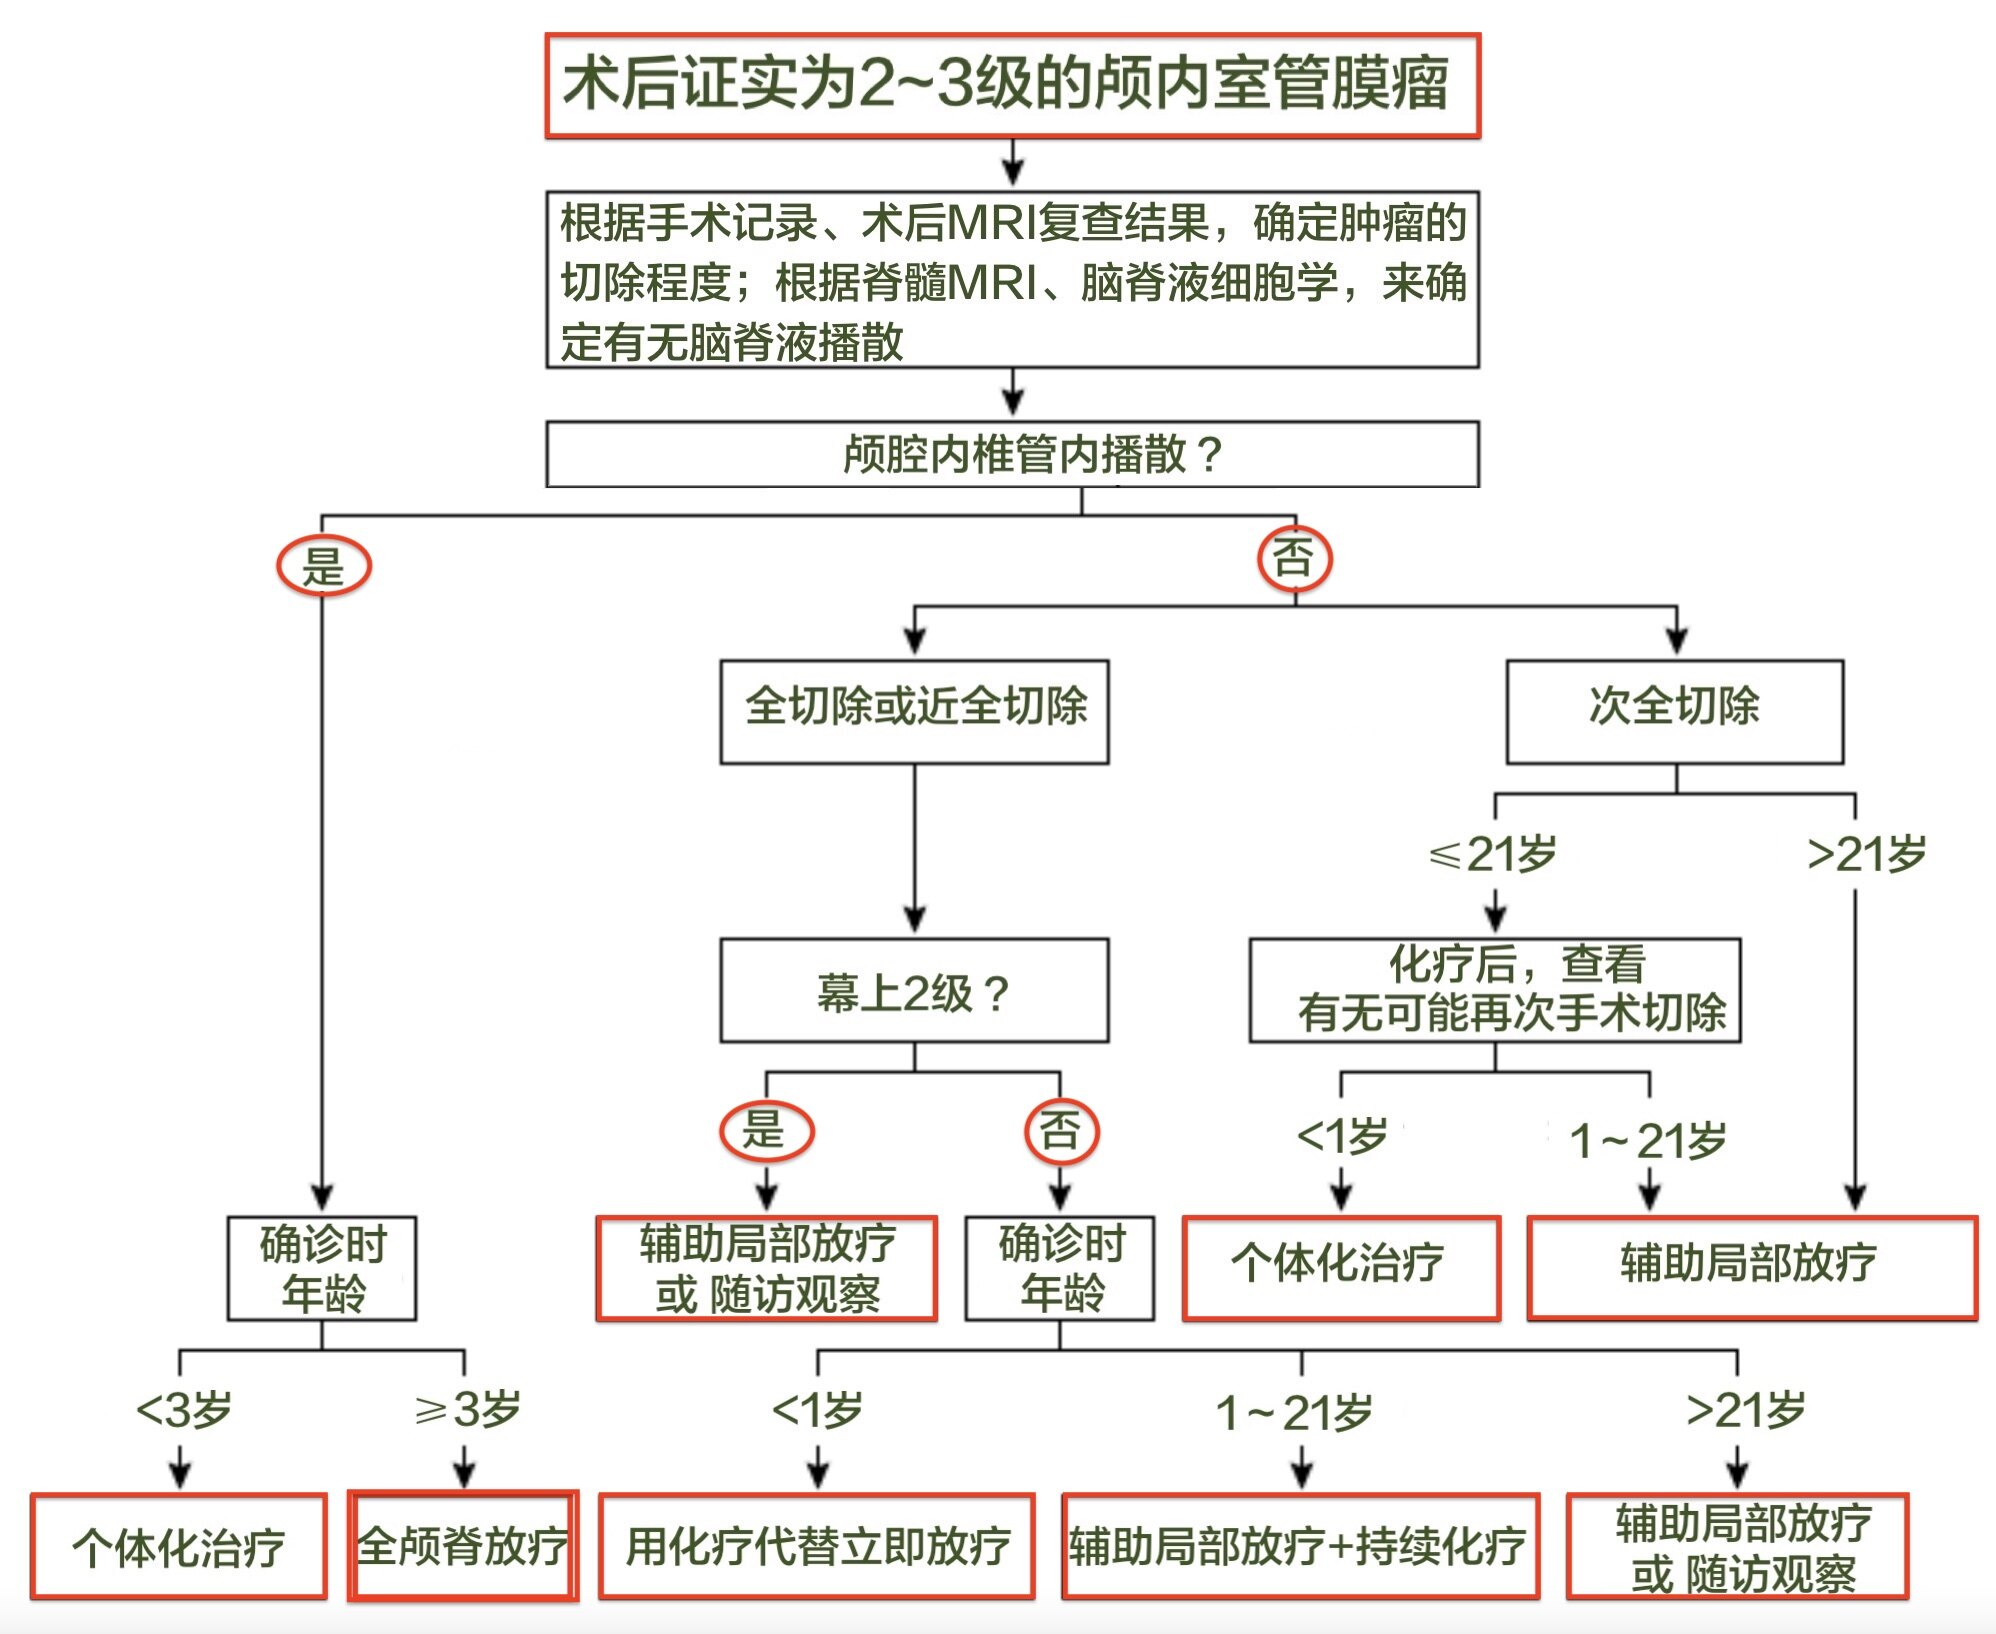

●对所有颅内室管膜瘤患者都推荐最大程度安全切除肿瘤(Grade 1B)。虽然全切是手术目标,但由于脑干受累或肿瘤邻近其他重要结构,全切不一定可行。

●对于超过1岁的、且接受全切、或近全切的颅内室管膜瘤患者,推荐术后立即予以局部放疗(Grade 1B)。

但除外以下情况:

?接受全切的1~3岁患儿可在术后采用化疗来代替立即放疗,以避免放疗的神经系统并发症但这只能用于正式的临床试验中。

?幕上Ⅱ级室管膜瘤可在全切后予以观察处理,而不是立即放疗。

●对于接受次全切除的颅内室管膜瘤患者,建议术后化疗,若条件允许随后可行二次探查手术,继以局部辅助放疗而不是术后立即放疗(Grade 2C)。

●对于小于1岁的颅内室管膜瘤患儿,建议采用辅助化疗作为推迟辅助放疗的过渡措施(Grade 2C)。

任何级别的室管膜瘤,在全切除后都应直接接受适形放疗,除非患者参加经审批的前瞻性临床试验或者年龄非常小(例如<1岁)。

大多数Ⅱ级和Ⅲ级颅内室管膜瘤患者在全切或近全切除后的标准治疗为术后放疗,以降低局部复发风险。

主要的例外如下:

①年龄极小的儿童(<1岁),通常可给予化疗以尽量避免放疗对发育的潜在不良影响;以及

②Ⅱ级幕上室管膜瘤全切的患者,这类患者预后良好可考虑观察处理而不是术后立即放疗。

接受次全切除的患者的无进展生存期和总生存期总是更差。建议这些高风险患者在术后接受短期化疗,若条件允许可行二次探查手术,然后再予以适形放疗。

患者通常在术后接受1~4个周期的多药化疗,然后复行MRI检查确定有无残余肿瘤,若有残余肿瘤则评估能否安全切除。有可能切除残余肿瘤的患者可先接受二次减瘤手术,再行辅助局部放疗。

建议采用辅助化疗作为推迟辅助放疗的过渡措施。

化疗后仍有残余肿瘤的患儿可考虑接受二次探查手术,这些患儿应尽可能在三级专科医疗中心接受治疗。

在1岁以上患儿中,局部放疗对局部控制和长期生存的潜在益处通常大于风险。